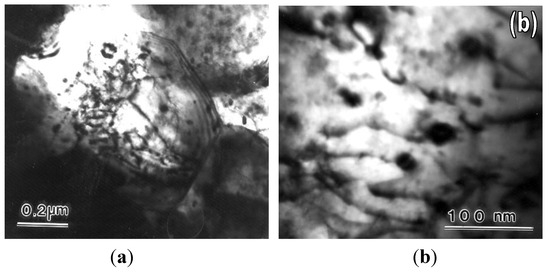

In magnesium alloys, the components used modify the alloy properties. For magnesium implants in contact with bone, rare earths alloys are commonly examined. These were shown to have a higher corrosion resistance than other alloys and a high mechanica...